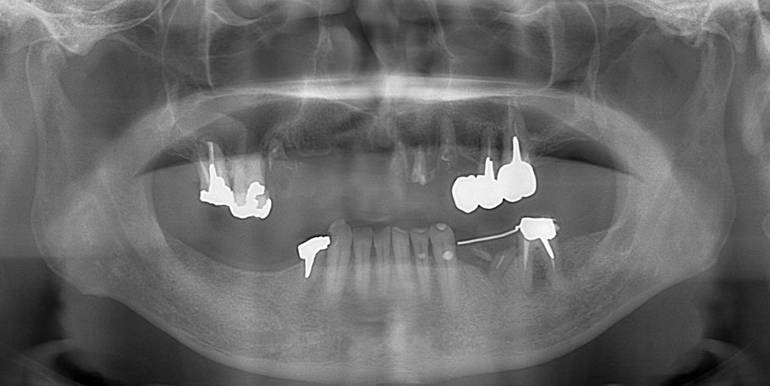

よく噛めなかったケース

術前。62歳男性。仮の歯の入っている上顎前歯部は抜歯するしかない状態。右下がない為右上臼歯が伸びだしていました。入れ歯では咬めないのでインプラントを希望され紹介されて来院されました。

術前のパノラマレントゲン写真。仮歯を支えている4本の歯は根が残っているだけで抜歯の必要がありました。

63歳術後のパノラマレントゲン。インプラントはスプラインツイスト